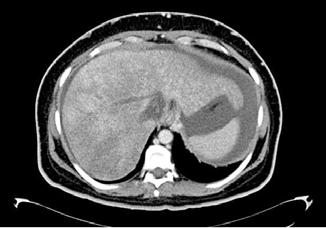

Se realizó una tomografía computarizada (TC) con contraste de forma emergente, que mostró una disección aórtica iatrogénica tipo A focal de origen en la zona 0 del cayado con extensión al tronco braquiocefálico derecho (1) sin afectar al resto de troncos supra-aórticos, cayado o aorta descendente (Figuras 1 y 2); además del hematoma

Figuras 1 y 2: Prótesis aórtica migrada y disección aórtica focal tipo A, de origen en la curvatura menor del arco aórtico (zona 0) hasta la bifurcación de la arteria braquiocefálica derecha; sin afectación de del resto de troncos supra-aórticos, del resto del cayado aórtico o de la aorta descendente.